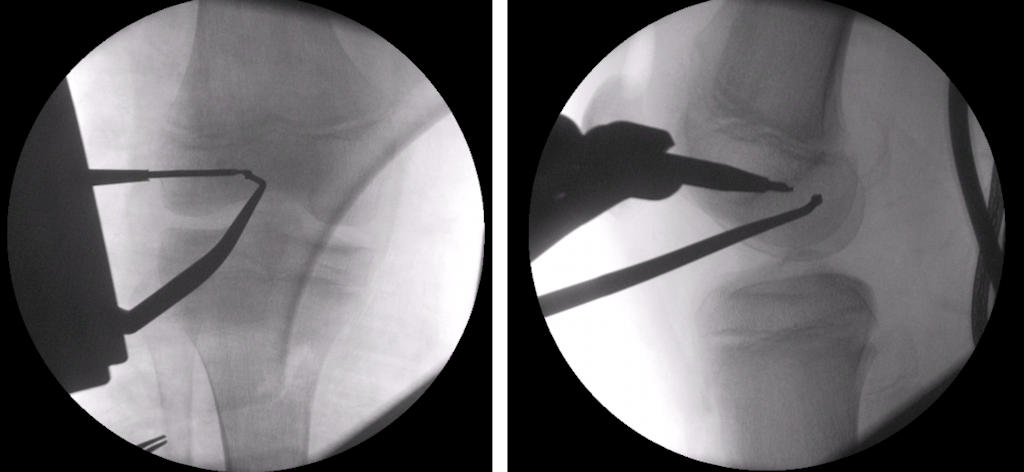

Büyümesi devam eden çocuklarda, fizis koruyucu cerrahi adı verilen teknikler ile büyüme kusuru riskinin en aza indirilmesi mümkündür. Bu tekniklerle yapılan ön çapraz bağ cerrahisinde kullanılan tünellerin yerleşimi, açısı ve tespit yöntemi erişkinlerden farklılıklar gösterir. Eğer bir kiriş dokusu kullanılarak bağ onarımı yapılacaksa, çocuğun kendi dokusunun (otogreft) kullanılması tercih edilir (Resim 2). Ameliyatın her aşamasında, röntgen (skopi) kontrolü ile büyüme kıkırdağına zarar verilmediği doğrulanmalıdır (Resim 3). Başka insandan alınan dokular (allogreft) ile yapılan bağ onarımının başarısızlık riski bu yaş grubunda 4 misli daha fazladır. Birçok hayvan deneyi ve insan çalışmasında, uygun teknikler kullanıldığında müdahale gerektiren büyüme kusuru riskinin %1-2’den daha düşük olduğu gösterilmiştir. Çoğu çocukta, cerrahi sonrası ortaya çıkabilecek büyüme değişiklikleri ya hiç yoktur ya da gözle fark edilmeyecek derecede azdır ve herhangi bir tedavi gerektirmez.